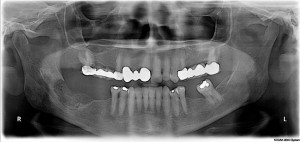

Наиболее ранние рентгенологические признаки заболевания могут быть обнаружены через 8—10 дней от начала клинических проявлений. Выявляется переход воспалительного процесса с периапикальных тканей на тело нижней челюсти. Определяется частичное разрушение кортикальной пластинки, структура прилегающей части нижней челюсти перестраивается, появляются участки остеопороза и остеосклероза, которые, постепенно уплотняясь, окружаются демаркационным валом и превращаются в секвестры разной формы и величины. Большую опасность представляет переход воспалительного процесса на ветвь челюсти и мыщелковый отросток, так как в головке челюсти находится ее ростковая зона. Возникающий при этом артрит может привести к недоразвитию нижней челюсти или анкилозу сустава.